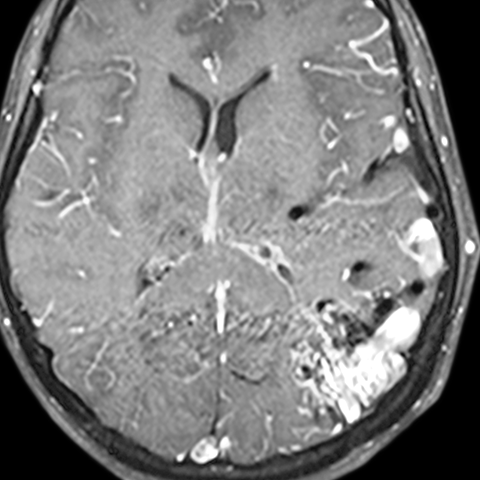

Cerebral AVM [3 of 3]